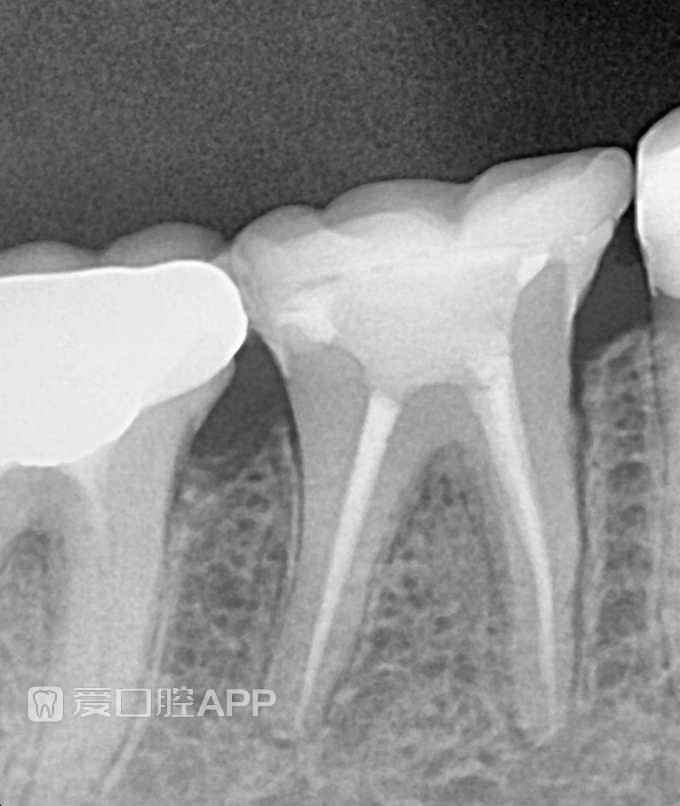

[病例] 看个根充+覆盖嵌体修复 —— 下颌第一磨牙

看个根充+覆盖嵌体修复 —— 下颌第一磨牙

by Asmaa Al-talla